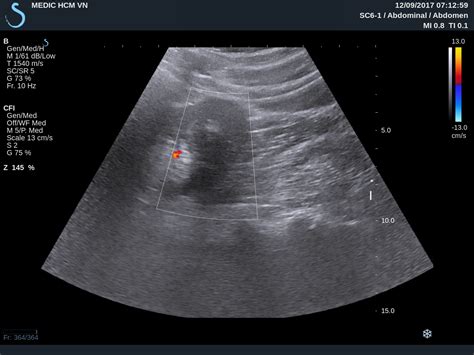

In the vast majority of cases, a Kidney AML tumor is asymptomatic, especially when small. It is frequently discovered incidentally during an ultrasound or CT scan performed for an unrelated health concern. However, if the tumor grows large or begins to bleed, symptoms may manifest, requiring prompt medical attention.

Diagnosing a Kidney AML tumor involves various imaging modalities to assess the size and character of the lesion. A CT scan with contrast or an MRI is typically the gold standard because these scans can identify the presence of fat within the tumor—a hallmark characteristic of an angiomyolipoma.

Ultrasound Initial screening; helps differentiate solid masses from cysts.